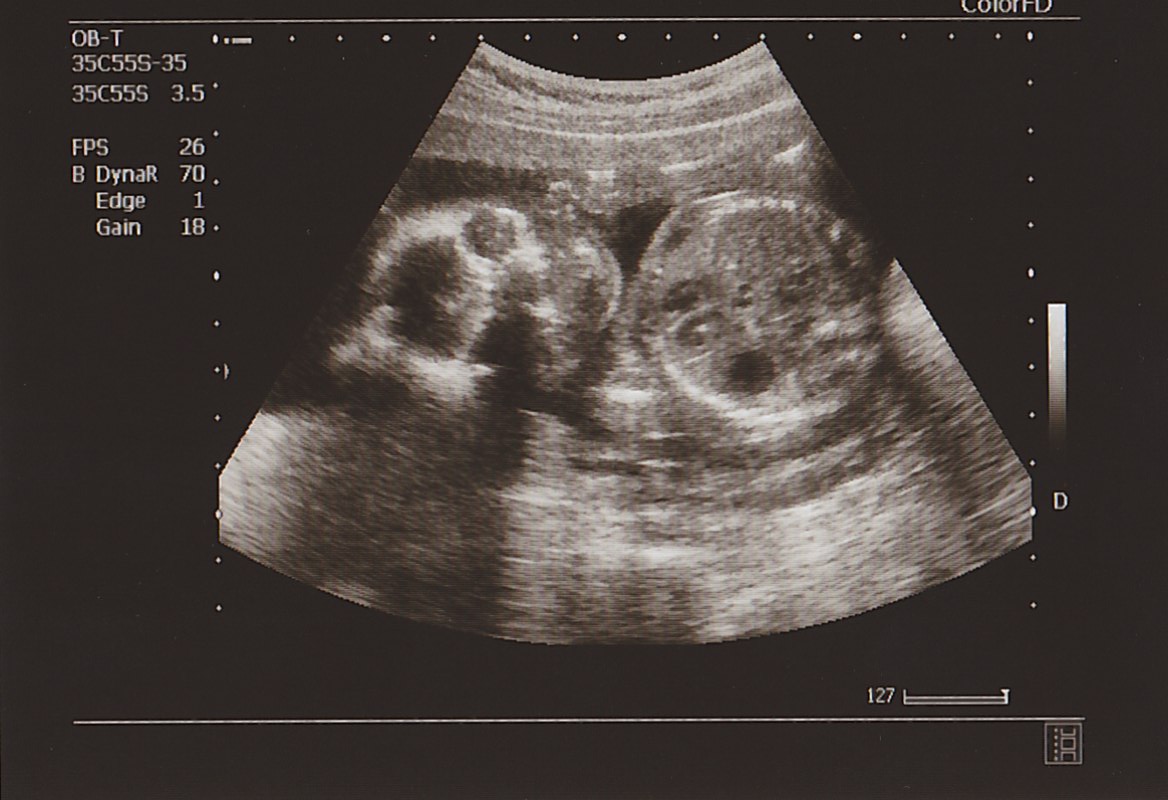

いま モンちゃんは おなかのなかで

柔軟体操 みたいに

2つに 折りたたまっているような 格好を

しているようです。

もう エコーに

全身を 映すことができないくらい

おおきく 育っています。

▲ こっち 見てるよ~!

左半分が あたま、 右半分が ボディ。

このエコーでは 手足は 映っていませんが

足のかたちも シッカリ 見えたし

おてては ガッツポーズ スタイルで

上に 下に と 動かしていました。

げんき げんき!